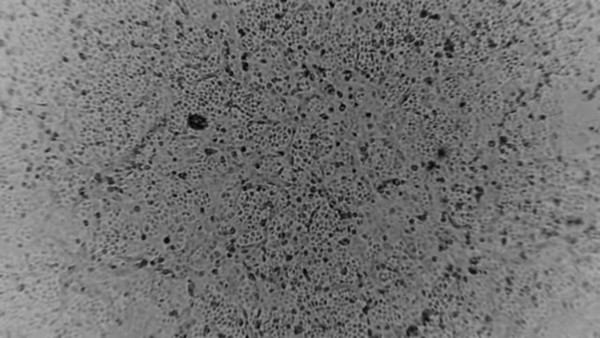

![호주에서 배양한 신종 코로나바이러스사진. 질병관리본부는 5일 국내에서도 환자로부터 바이러스를 분리하는데 성공했다고 밝혔다. [사진=뉴시스]](https://cdn.nvp.co.kr/news/photo/202002/201902_202112_5840.jpg)

신종 코로나 바이러스가 세계를 강타하자 자극적인 영상과 소문이 인터넷에 떠돌아 공포가 확산되고 있다. 이러한 가짜뉴스때문에 국민들의 불안은 더욱 커져가고 있다.